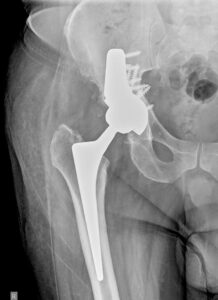

- Ακτινογραφία που εκ πρώτης όψεως δείχνει να μην έχει σοβαρό πρόβλημα, όμως έχει τεράστιο περιπροθετικό κάταγμα της κοτύλης. Έχει αποκολληθεί το εμφύτευμα από τη θέση του και έχει αποσπασθεί μαζί με ολόκληρο το οστικό οπίσθιο τοίχωμα της κοτύλης

- Δυσδιάστατη ακτινογραφία όπου φαίνεται η μετατόπιση του εμφυτεύματος της κοτύλης και το σπασμένο οπίσθιο τοίχωμα.